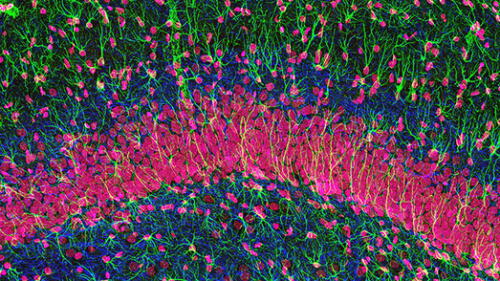

El cerebro sí produce miles de neuronas nuevas incluso después de los 80 años